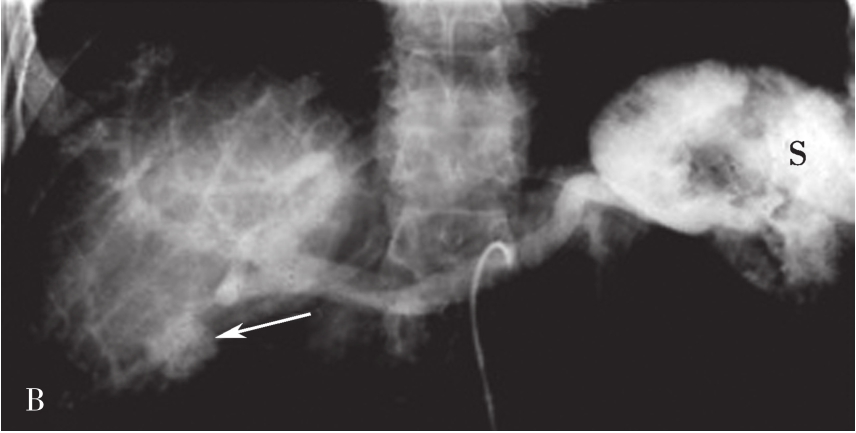

常规腹部平片对肝硬化诊断价值非常有限,但胃肠道钡餐检查可显示中晚期肝硬化患者食管、胃底蚯蚓状扩张的静脉。食管静脉曲张是门静脉高压的重要并发症,最主要见于肝硬化、门脉系统的血栓形成及上腔静脉综合征。

上消化道钡餐检查可见食管及胃底多发串珠状或蚯蚓状充盈缺损,食管腔轻度扩张,管壁蠕动减弱,病变常始于食管下段,后延及食管中段及胃底,极少数可波及食管上段。按静脉曲张的范围、程度及食管蠕动功能分为轻度、中度、重度。①轻度:静脉曲张最初局限性于食管下段,表现为黏膜皱襞稍增宽,可呈浅锯齿样表现。管腔可收缩排空。②中度:随着静脉曲张的发展,曲张范围超过下段累及中段。静脉增粗迂曲突向管腔,正常平行的黏膜皱襞消失,代之以纵行粗大结节样条状影,进一步表现为串珠状或蚯蚓状充盈缺损,食管边缘凹凸不平,由于黏膜下明显静脉曲张,食管腔被撑开而略显增宽,食管收缩欠佳,排空稍延迟。③重度(图5-21-34):后期静脉曲张扩展到中上段,甚至食管全长。严重的曲张静脉占据食管壁,并使肌层受压迫而退变,食管明显扩展,不易收缩,腔内见形态不一的圆形、环状或囊状充盈缺损,管壁蠕动明显减弱,排空延迟,但管壁仍柔软可扩张。

图5-21-34 重度食管静脉曲张钡剂检查结果

食管全长可见不规则蚯蚓状和结节状充盈缺损,食管明显扩展,蠕动明显减弱,排空延迟,管壁尚柔软